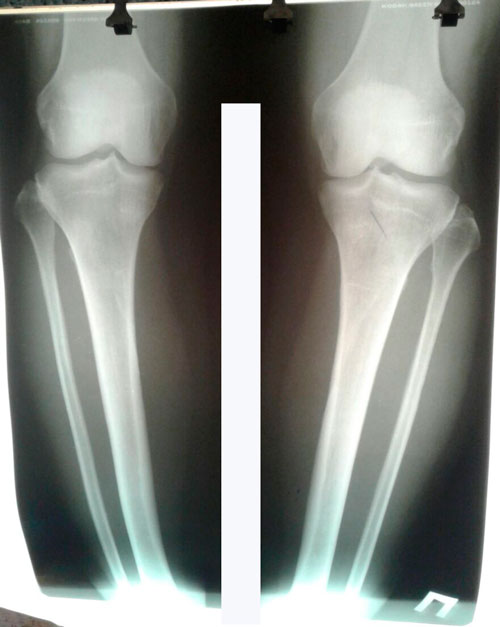

Исходник - 44 года.

Дата операции 21.03.2017г.

Дата снятия аппаратов 25.07.2017г.

Срок лечения 123 дня.